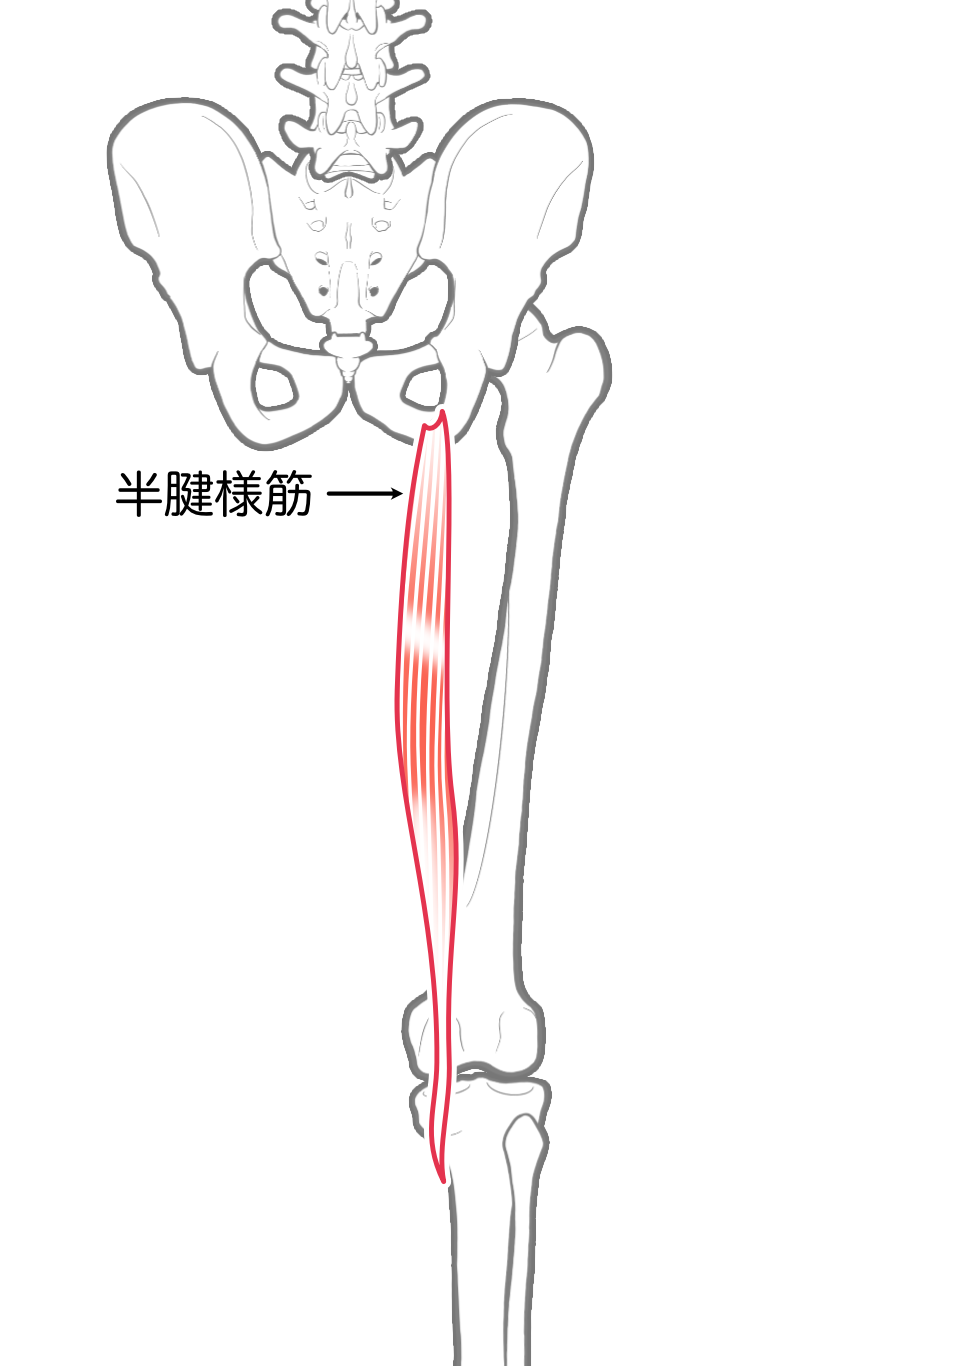

半腱様筋

| 起始 | 坐骨結節 |

| 停止 | 脛骨上部内側面(鵞足) |

| 神経 | 坐骨神経L(4),5, S1,(2) |

| 作用 | 膝関節屈曲,内旋 |